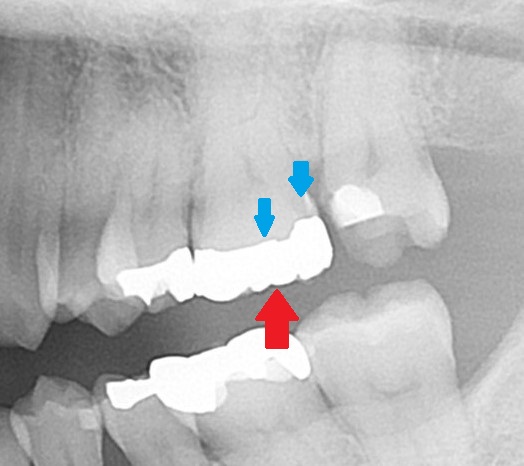

実際に虫歯があったのは、

青い矢印の所に虫歯が広がっていました。(後で銀歯の下の状態もお見せします)

では、レントゲンでも分かりにくい、この歯の虫歯をCT検査だったら分かるのでしょうか?